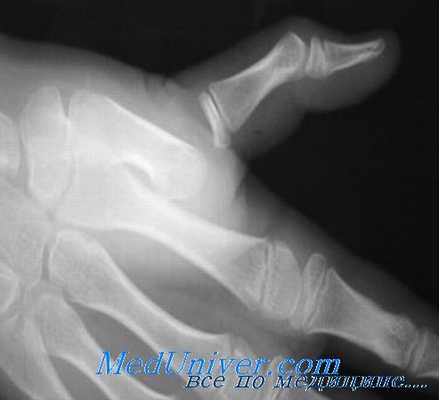

При сложном вывихе палец находится в вынужденном положении умеренного разгибания, активное сгибание отсутствует. Пальпаторно на ладонной поверхности будет определяться выступающая головка пястной кости. При рентгенографии определяется расширенная суставная полость, в которой нередко определяются сесамовидные косточки, что подтверждает ущемление ладонной пластинки.

Вывихи в I пястно-фаланговом суставе в большинстве случаев являются тыльными, и могут быть простыми или сложными. Как и при вывихах в остальных ПФС, механизм травмы основан на резком переразгибании I пальца. При этом происходит разрыв ладонной пластинки проксимальнее, дистальнее или на уровне сесамовидных косточек. Как правило, тыльные вывихи можно устранить путем закрытого вправления, но интерпозиция сухожилия длинного сгибателя пальца, обычно в области локтевого края головки пястной кости, или других мягкотканых или костных образований со стороны лучевого края препятствует репозиции суставных поверхностей.

Выявляемая при рентгенографии интерпозиция сесамовидных косточек обычно ассоциируется со сложным невправимым вывихом, тогда как перелом сесамовидных косточек, как правило, свидетельствует о возможности успешного закрытого вправления.